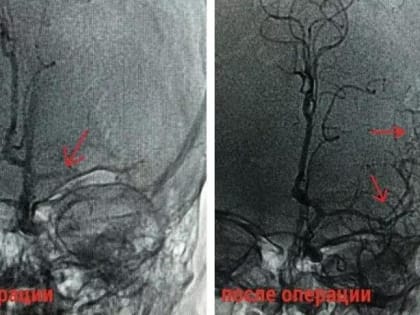

Врачи в Домодедове спасли 22‑летнюю девушку с инсультом

В Домодедовскую больницу бригадой скорой помощи была доставлена 22-летняя девушка с признаками ишемического инсульта – резкого нарушения кровоснабжения мозга,